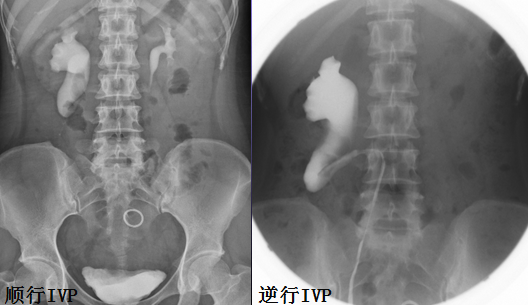

IVP 是显示囊肿的基本方法

输尿管下端扩张, 如眼镜蛇头样

膀胱内有圆形透亮的充盈缺损边缘光整, 常伴有输尿管内的造影剂影, 形成「光晕征」